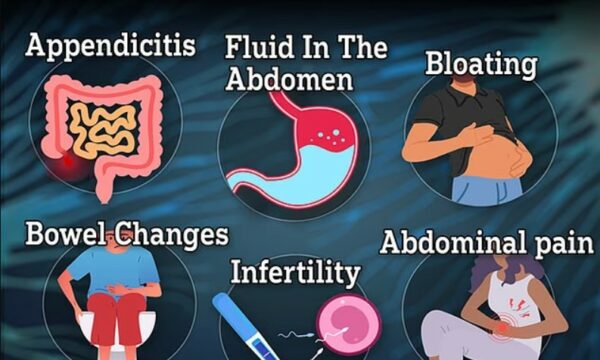

Shenjat e fshehura të një kanceri që po rritet më shpejt se kanceri i zorrës së trashë tek të rinjtë

Shenjat e fshehura të një kanceri që po rritet më shpejt se kanceri i zorrës së trashë tek të rinjtë